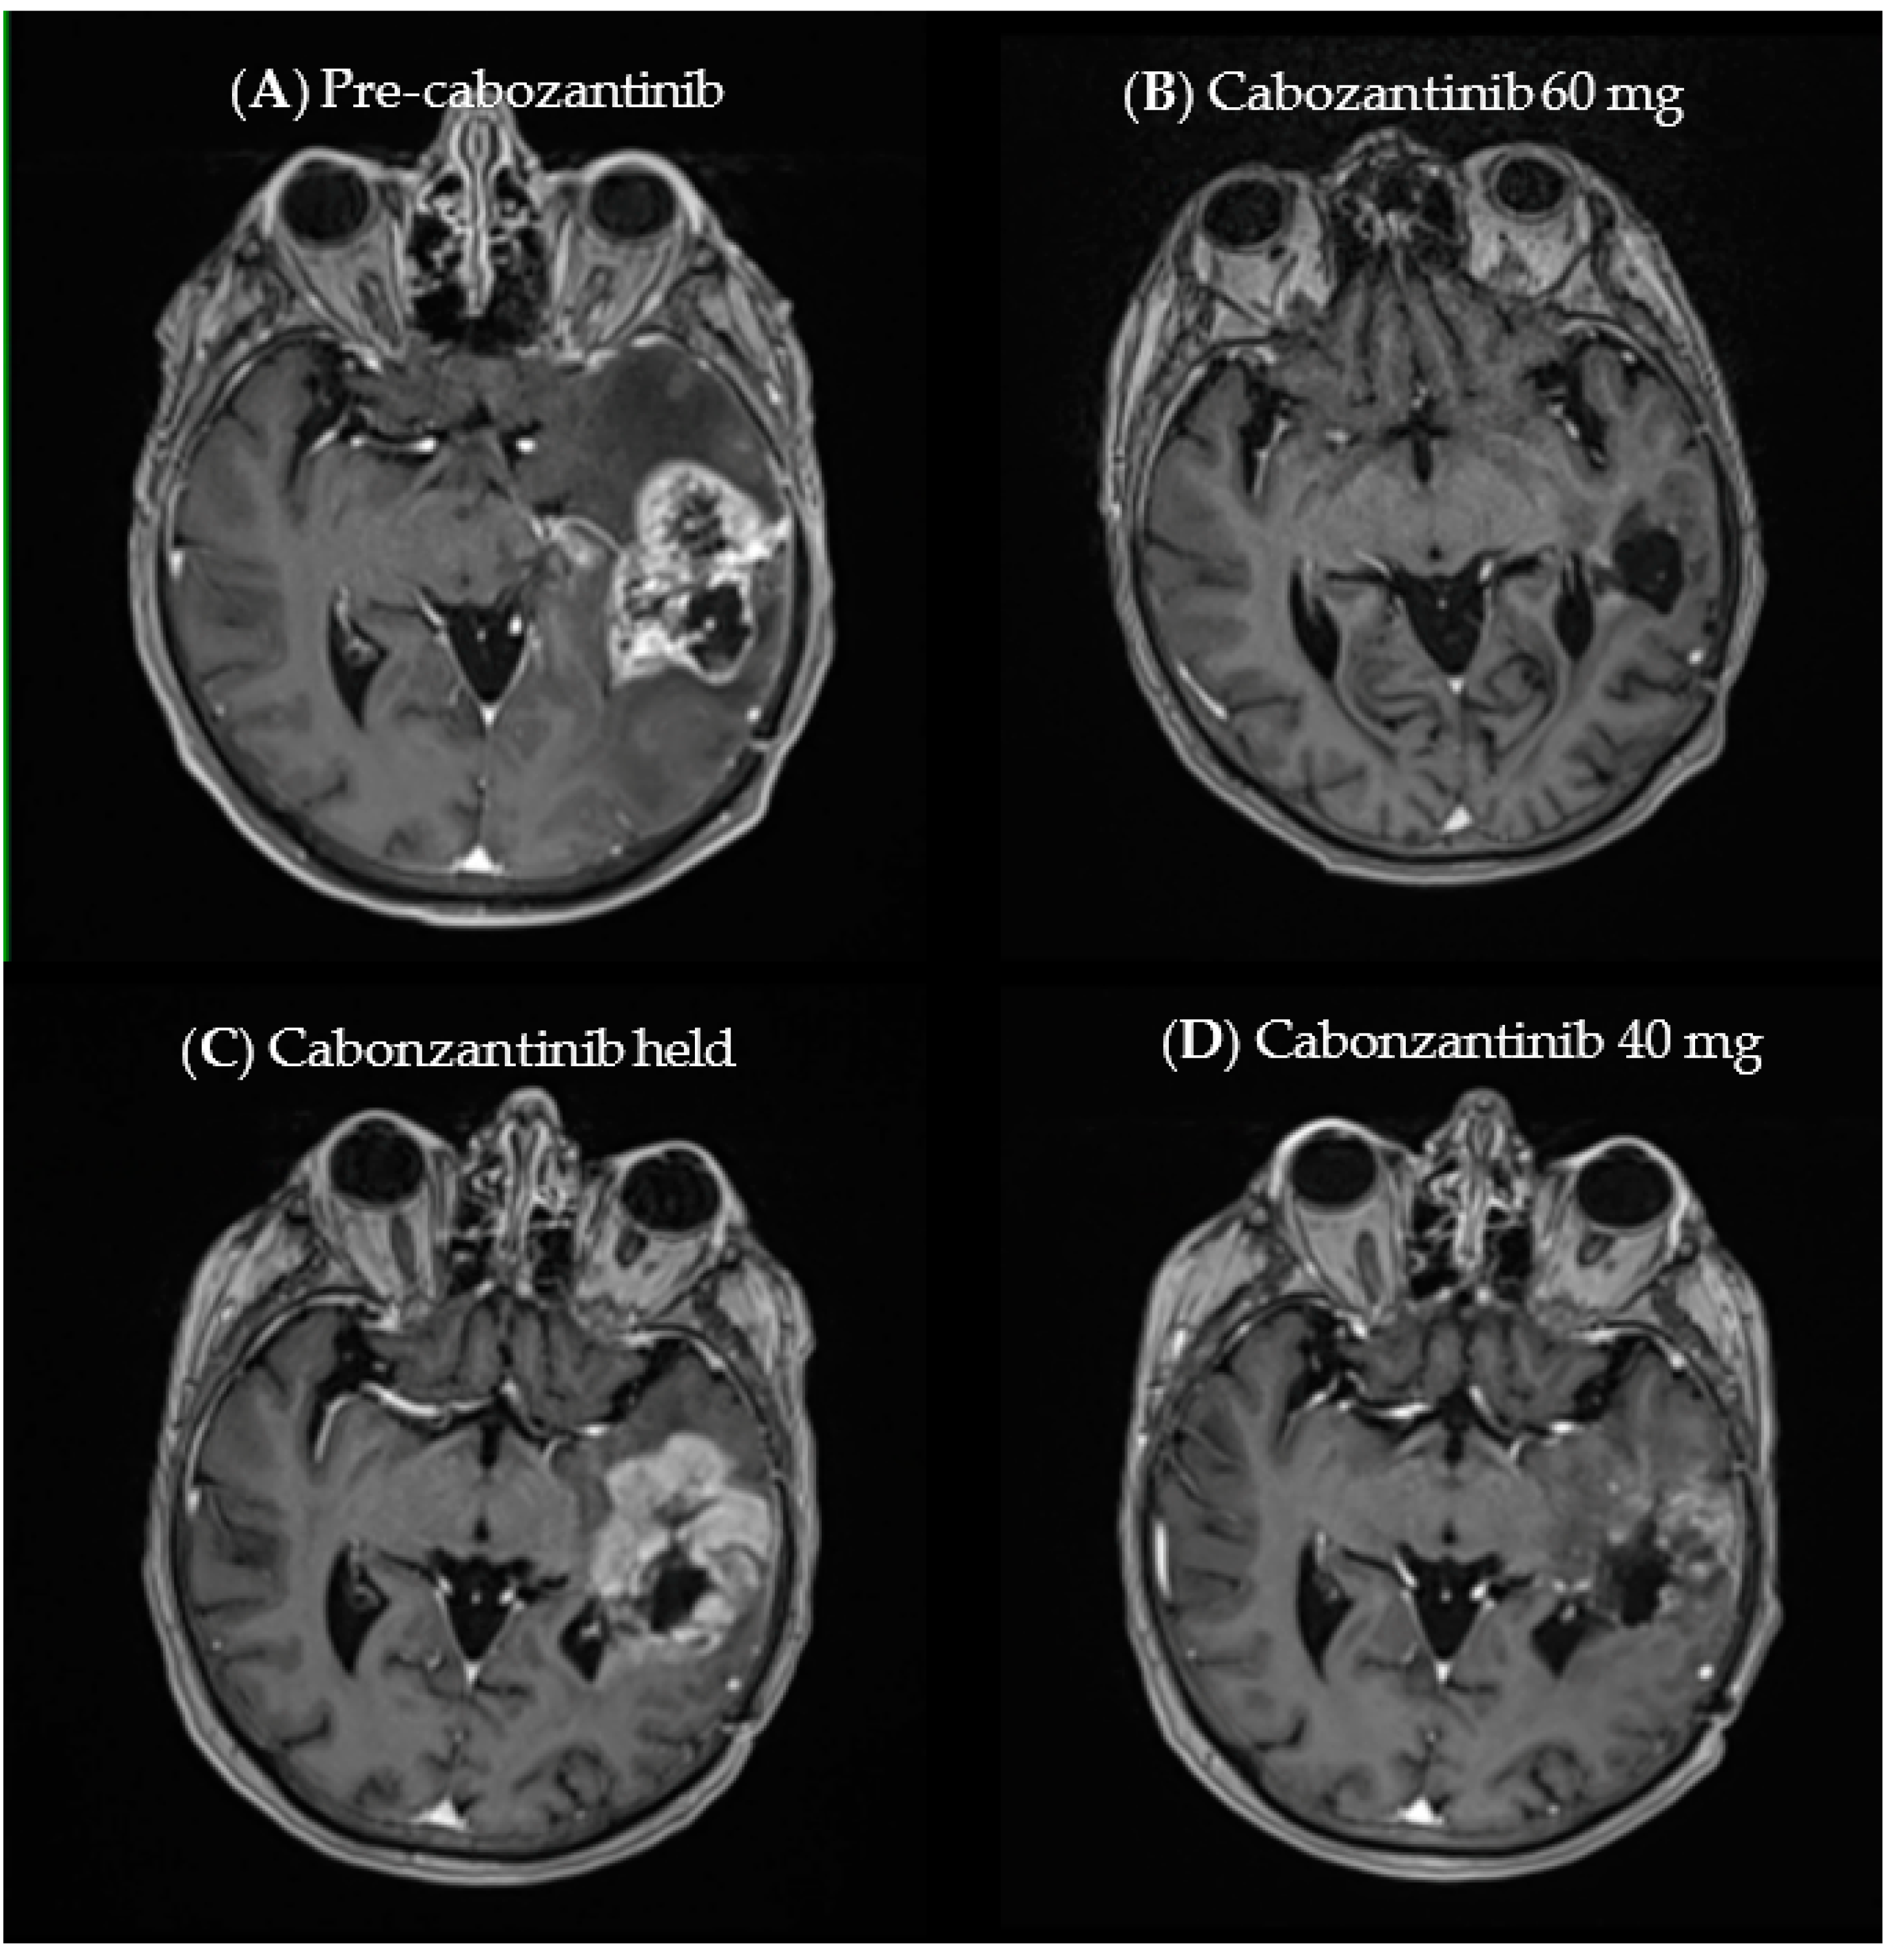

3.3. Case Example

| MET exon 14 deletion MET amp | Cabozantinib | 100 | 25.4 |